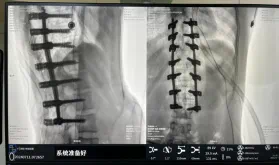

據悉脊柱側彎手術治療后可以保持軀干平衡,改善外觀并防止畸形進一步發展。患者的生活質量得到提高,進而減少脊柱過度畸形可能帶來的疾病的發生率,外觀上的積極變化往往也能帶來患者心理與精神的積極變化。臨床上會綜合考慮患者的年齡、側彎程度、進展趨勢、骨質條件、鄰近節段情況、手術節段等因素,合理采用個性化的手術方式進行治療。然而,由于脊柱神經血管密布,手術操作相對復雜,手術難度高、風險大,傳統脊柱側彎的手術方式往往有較高的神經或脊髓損傷風險。故此次科室決定開展機器人輔助導航下脊柱側彎矯形、植骨融合內固定手術。術前,醫生團隊在機器人多維度圖像融合智能手術規劃功能的輔助下,預先規劃了理想的置釘路徑。術中,天璣骨科手術機器人準確遵循術前規劃,根據配準結果,實時定位并準確執行置釘操作,所有導針均用電鉆置入,一次性成功,協助醫生順利完成手術。最終,在麻醉科、手術室密切配合下,歷時3小時成功完成側彎矯形術,出血量僅500ml。術后,患者恢復良好,大小便及下肢神經運動感覺正常。

圖為置釘后

此次在充分保證患者安全和手術效果的前提下使用機器人輔助下手術的成功實施,大大降低了高難度手術的風險,并進一步減輕了患者手術創傷、縮短了康復時間。這也標志著南方醫院贛州醫院脊柱外科治療個性化、精準化、智能化水平進一步提升。